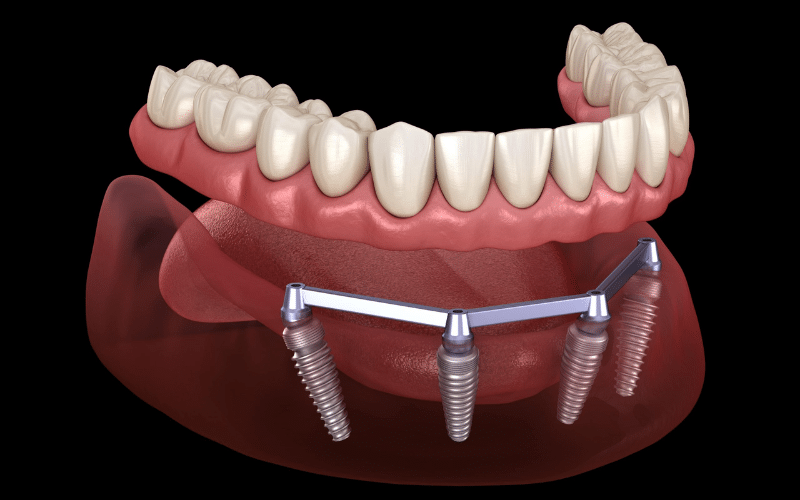

Dentures are a set of false teeth that can be removable or fixed. Removable dentures are held in place by suction or a dental adhesive, while fixed dentures can be attached to the jawbone using dental implants. Dentures come in both full and partial sets and are made from either acrylic resin or metal for durability.

Dental implants are titanium rods that are surgically implanted into the jawbone. These rods act as artificial tooth roots and provide a strong foundation for dental restorations. Implants can be used to support single crowns, bridges, or dentures and they provide a natural-looking result with full functionality.